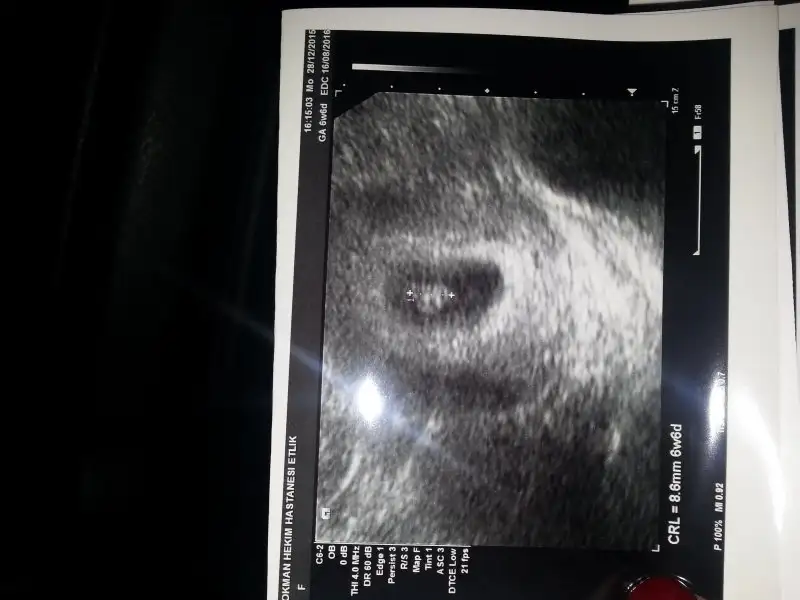

Benimkine cok benziyor hem kese hemde konumu olarak. Benim oglum oluyor insallah :)Bunuda yorumlayabilirmisiniz rica etsem